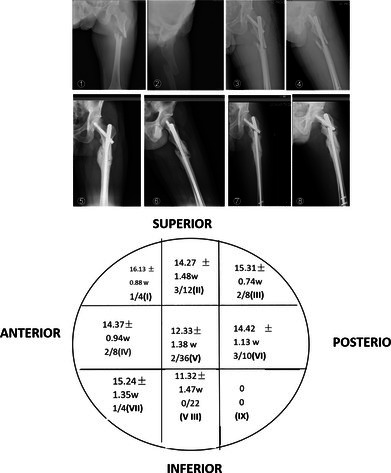

Results: Data from 104 patients (58 males, 46 females) with a mean age of 56.9 years were analyzed. Fracture healing was observed in 90 (86.5%) patients at an average time of 14.92 ± 1.81 weeks. The healing rate was significantly higher when the TAD and Cal-TAD were controlled within the 20-25 mm range (p < 0.05). Postoperative complications occurred in 14 (13.5%) cases [cephalad cut-off, n = 5 (4.8%); axial cut-off, n = 4 (3.8%); non-union, n = 5 (4.8%)]. Five (4.8%) complications occurred without internal fixation failure. The fracture healing time and incidence of complications differed among groups defined by TAD and Cal-TAD measurements, and were shortest and lowest, respectively, in the 20 mm < TAD/Cal-TAD < 25 mm group.

Conclusions: In our cohort, use of PFNA internal fixation for treatment of unstable femoral subtrochanteric fractures and placement of the spiral blade in the middle or lower 1/3 of the femoral neck did not increase the incidence of complications. Therefore, we propose that the TAD rule of 20-30 mm should not apply to subtrochanteric fractures, and TAD and Cal-TAD should be controlled within the range of 20-25 mm to reduce the incidence of complications.